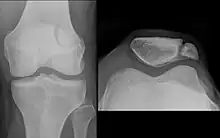

The patella (pl.: patellae or patellas), also known as the kneecap, is a flat, rounded triangular bone which articulates with the femur (thigh bone) and covers and protects the anterior articular surface of the knee joint. The patella is found in many tetrapods, such as mice, cats, birds and dogs, but not in whales, or most reptiles.

The patella is a sesamoid bone roughly triangular in shape, with the apex of the patella facing downwards. The apex is the most inferior (lowest) part of the patella. It is pointed in shape, and gives attachment to the patellar ligament.

The upper three-quarters of the patella articulates with the femur and is subdivided into a medial and a lateral facet by a vertical ledge which varies in shape.

In the adult the articular surface is about 12 cm2 (1.9 sq in) and covered by cartilage, which can reach a maximal thickness of 6 mm (0.24 in) in the centre at about 30 years of age. Owing to the great stress on the patellofemoral joint during resisted knee flexion, the articular cartilage of the patella is among the thickest in the human body.